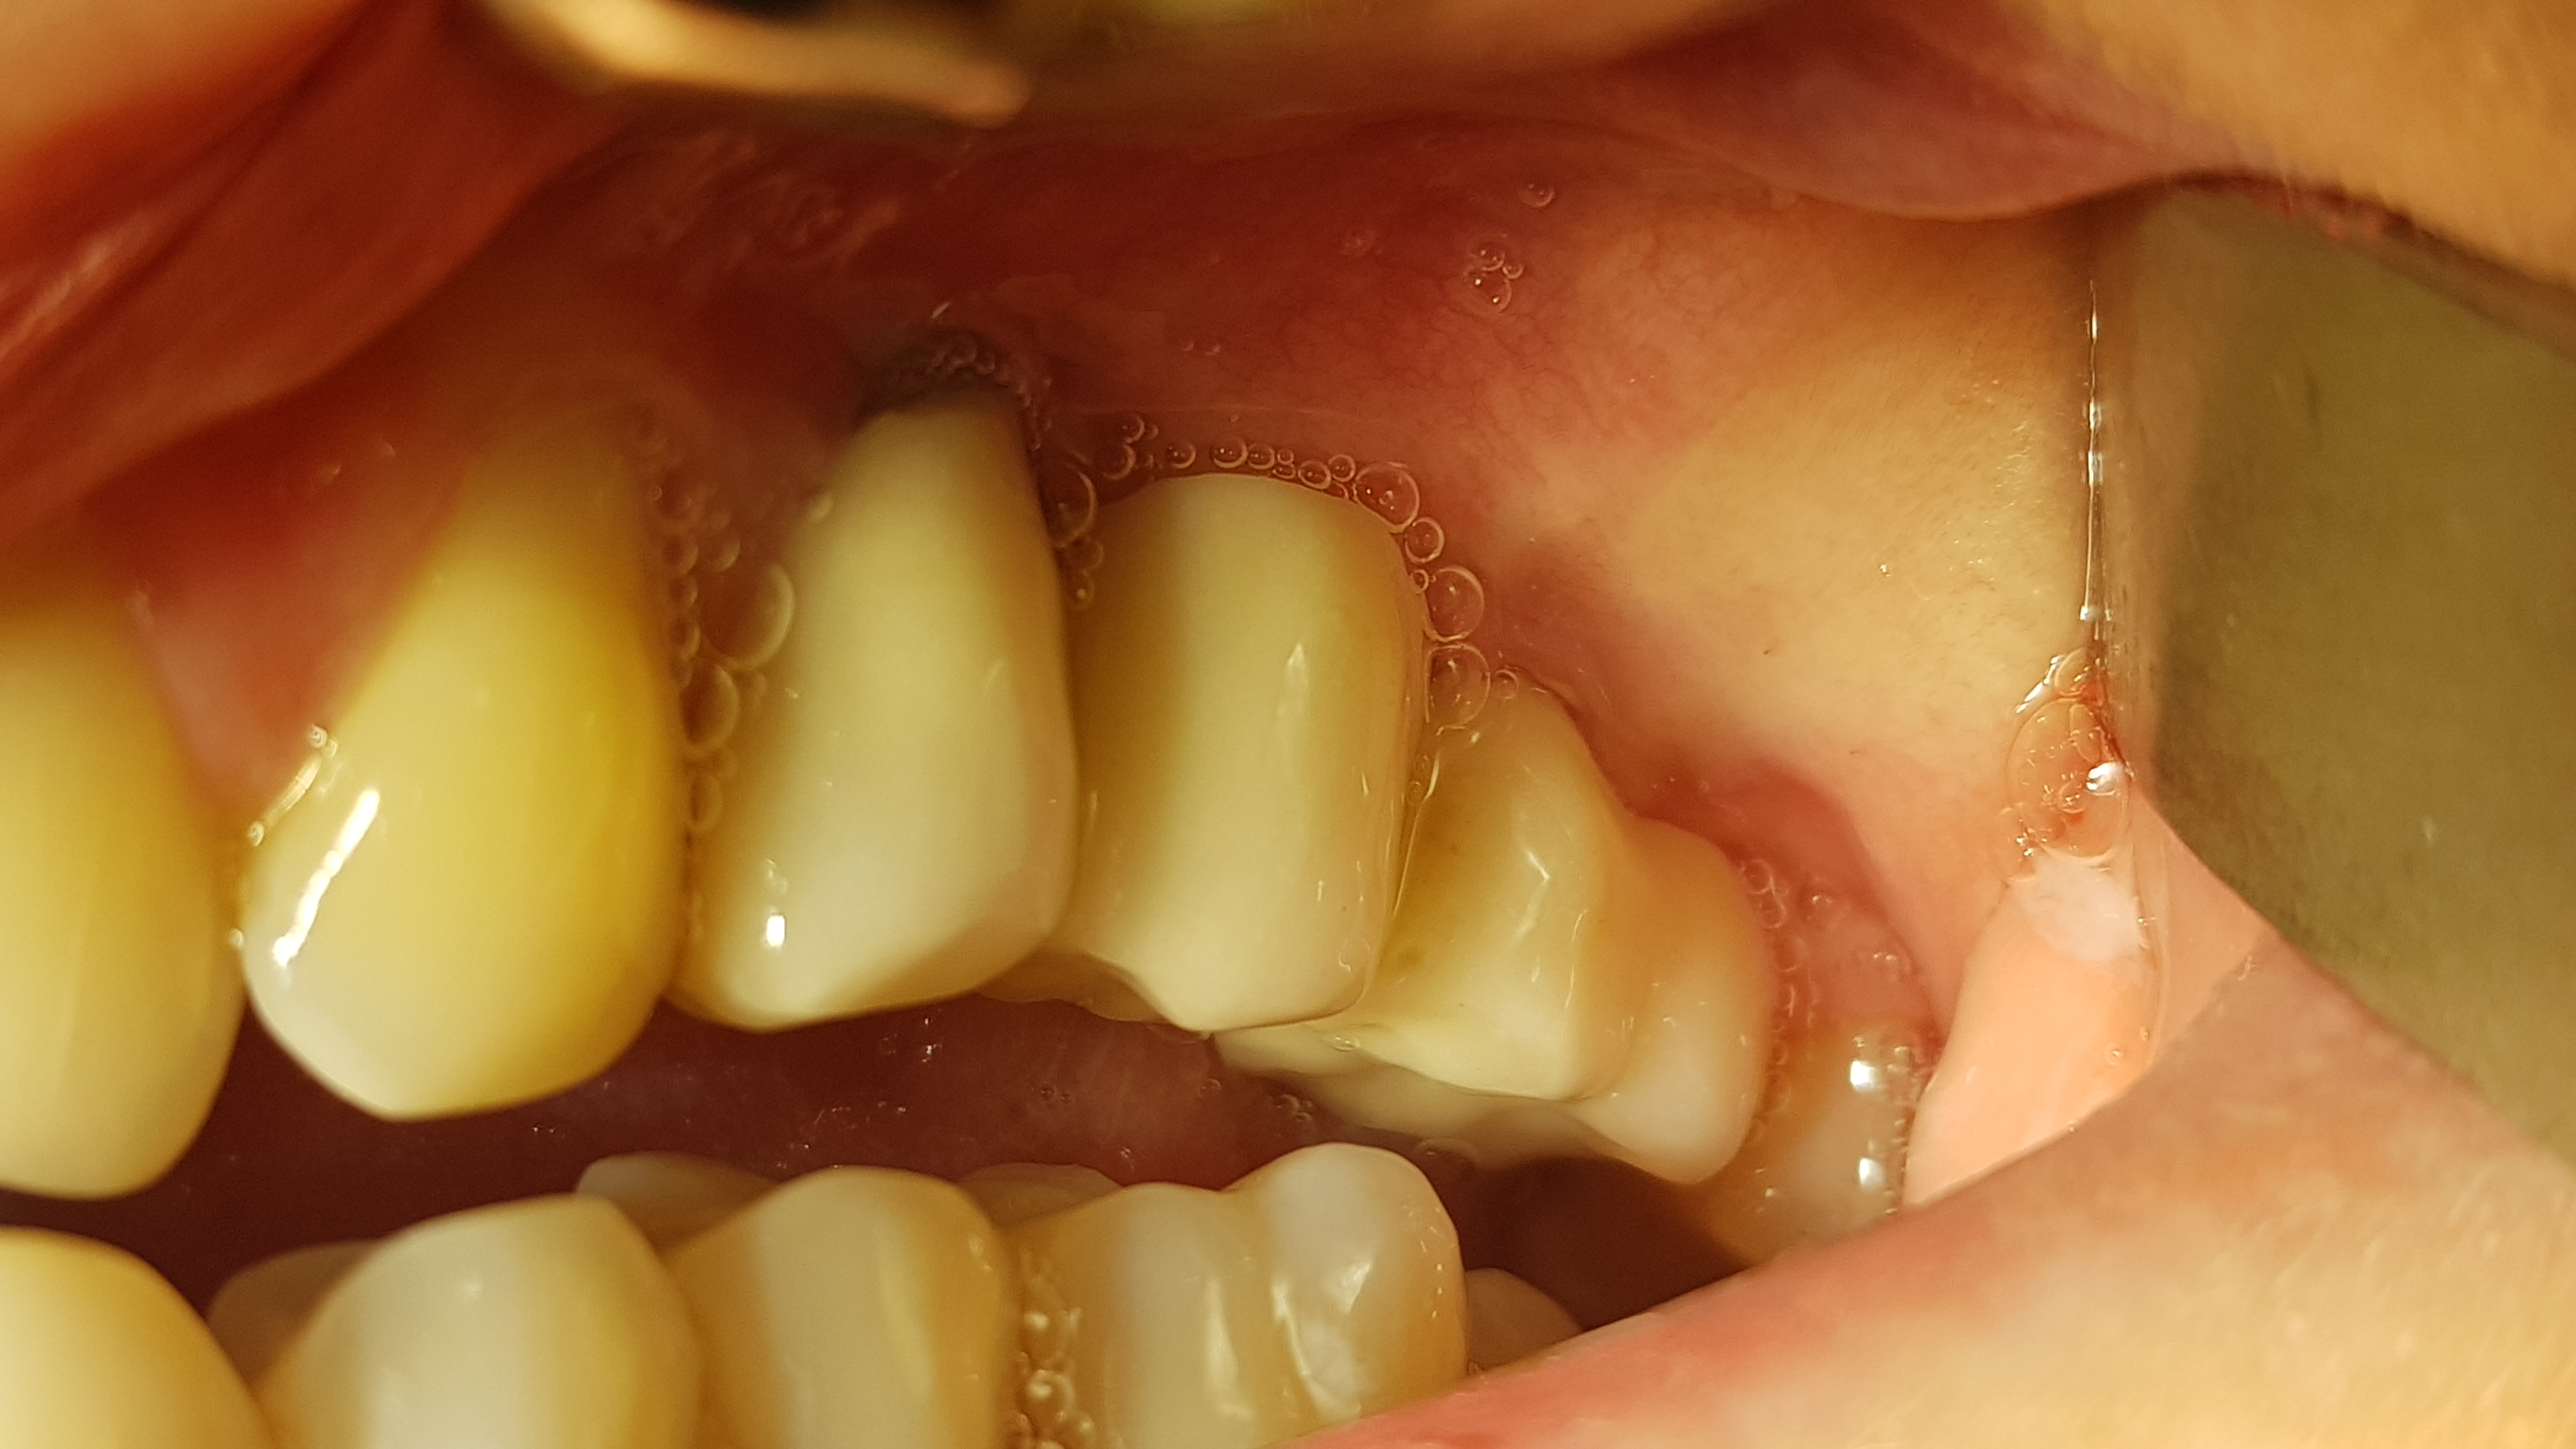

Kontrola po 12 miesiącach wykazała prawidłową strukturę kości i tkanek miękkich (ryc. 25, 26).

Ryc. 25. Kontrla rtg 12 miesięcy po obciążeniu funkcjonalnym.

Ryc. 26. Stan miejscowy 12 miesięcy po obciążeniu funkcjonalnym.

Ponadto nie odnotowano jakichkolwiek wtórnych powikłań zapalnych, co sugeruje taki sposób

postępowania w podobnych przypadkach wąskich wyrostków zębodołowych.